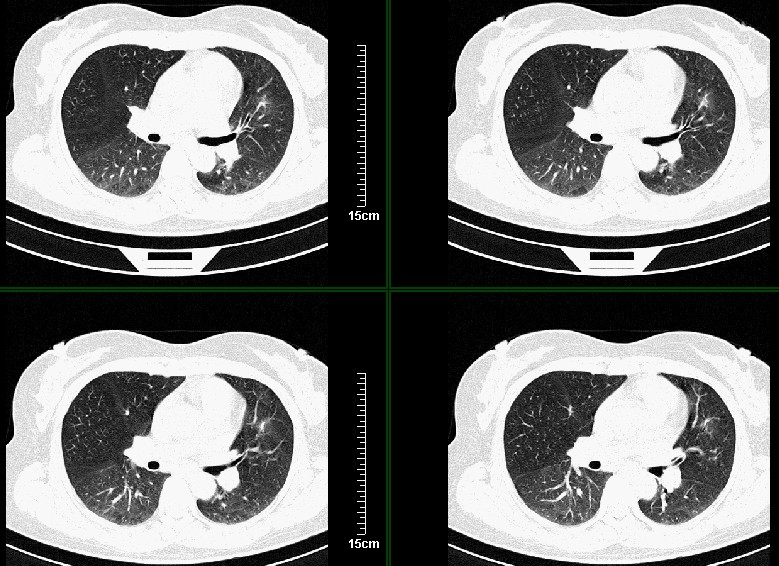

一周之后 复查结果 5mm扫描 40多岁 我们医院的护士

左肺上叶肿块,肺窗周围有“晕征”,纵隔窗有毛刺,临床资料???只能考虑占位???

第八幅图像,典型毛刺,像日本鬼子的膏药军旗一样,一看就不是个好东西